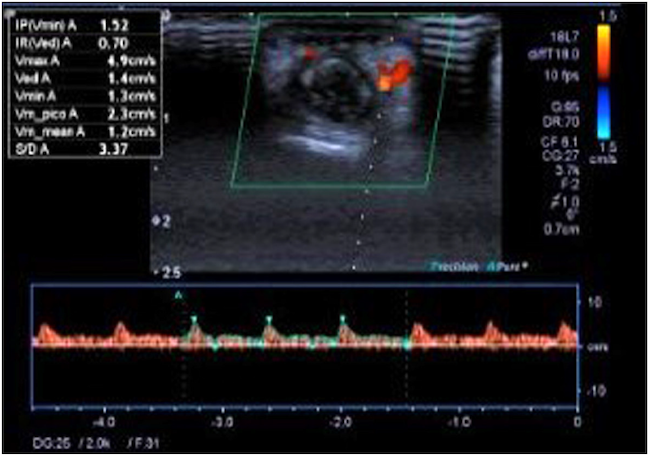

48 horas después del procedimiento endoscópico presentó lesiones dérmicas petequiales y necróticas en el cuarto dedo de la mano izquierda (Figuras 6 y 7), por lo que se le realizó una ecografía Doppler de miembro superior en la que se encontraron fluidos disminuidos con ondas parvus tardus en las arterias digitales palmares y dorsales del cuarto dedo de la mano izquierda (Figura 8). Fue valorado por dermatología y se realizó la toma de biopsia que dio como resultado vasculitis de pequeños vasos (paniculitis septal, infiltrado inflamatorio perivascular con predominio de neutrófilos, daño fibrinoide y hematíes extravasados). Recibió tratamiento de 3 pulsos de metilprednisolona 500 mg intravenoso, que posteriormente pasó a ser por vía oral con prednisona 60 mg hasta decalar y se retiró el corticoide; posteriormente se administró metronidazol 500 mg intravenoso por 14 días y mesalazina 3 g por vía oral hasta el momento. Actualmente, el paciente se mantiene asintomático sin signos de lesiones en las manos ni la lengua, y en remisión clínica de la CU, sin uso de corticoides, con mesalazina 3 g/día y tiene controles en consulta externa sin manifestaciones clínicas.